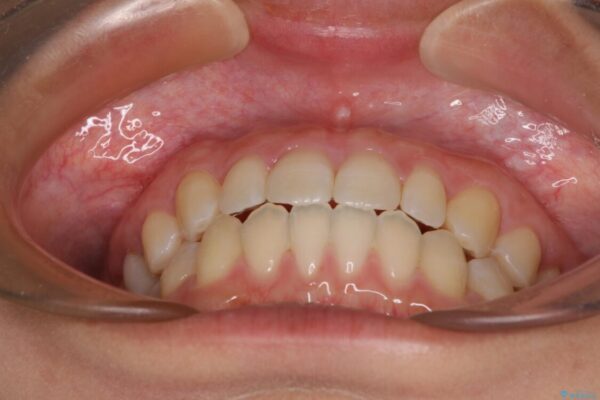

治療後について

空隙歯列(すきっ歯)は、舌の突出癖をある程度改善できたとしても、後戻りにより隙間が開きやすいと言われています。

裏側から細いワイヤーで保定するとともに、睡眠時のマウスピース装着を徹底していただくことで、後戻りを最小限にとどめます。

治療後

• 隙間だらけの歯列 インビザラインで改善 治療後画像